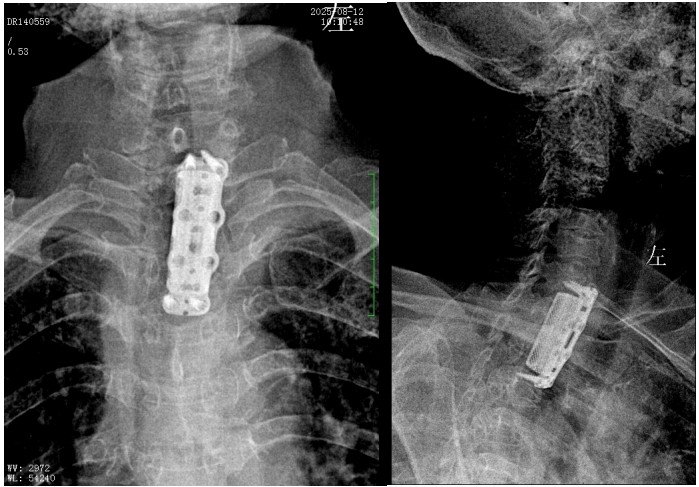

錢軍博士組織團隊進行了詳盡的術(shù)前討論,充分的術(shù)前準(zhǔn)備后,于8月10日為患者實施了“前路病灶清除、人工椎體植入、植骨融合內(nèi)固定術(shù)”。順利完成了徹底清除病灶,椎管減壓解除脊髓壓迫,矯正后凸畸形,重建脊柱穩(wěn)定性的手術(shù)目標(biāo)。

術(shù)后,脊柱外科醫(yī)護團隊為病人制定了快速康復(fù)方案,經(jīng)過精心治療與護理,李奶奶訴胸背部、雙上肢的疼痛癥狀較前明顯好轉(zhuǎn),晚上終于能睡個安穩(wěn)覺了。兩周后,李奶奶恢復(fù)良好,現(xiàn)已順利出院。